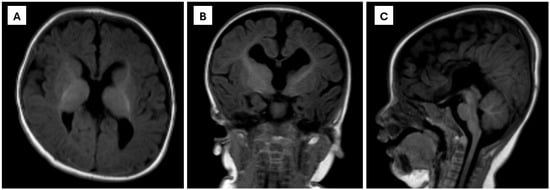

Background: Congenital disorders of glycosylation (CDG) are rare inborn errors of metabolism with multisystemic manifestations. SSR4-CDG is an ultra-rare X-linked subtype caused by pathogenic variants in SSR4, a component of the translocon-associated protein (TRAP) complex essential for protein translocation and N-glycosylation.

[...] Read more.

Background: Congenital disorders of glycosylation (CDG) are rare inborn errors of metabolism with multisystemic manifestations. SSR4-CDG is an ultra-rare X-linked subtype caused by pathogenic variants in SSR4, a component of the translocon-associated protein (TRAP) complex essential for protein translocation and N-glycosylation. Case presentation: We report a two-year-old Malaysian male presenting with global developmental delay, central hypotonia, microcephaly with complete agenesis of the corpus callosum, recurrent infections, bilateral vesicoureteral reflux, and failure to thrive. Growth parameters (weight, length, and head circumference) were persistently below the expected percentiles, indicating postnatal growth restriction. Initial metabolic and biochemical investigations for global developmental delay were unremarkable, apart from mild hyperammonemia. Transferrin isoform analysis demonstrated a type I CDG pattern, raising suspicion of a glycosylation defect. Results: Transferrin glycopeptide LC–MS/MS showed impaired N-glycan occupancy at both glycosylation sites (Asn432 and Asn630), with reduced fully sialylated glycoforms and increased non-glycosylated peptides. Targeted metabolomics using triple quadrupole LC–MS/MS revealed systemic abnormalities, including elevated arginine and phenylalanine, reduced glutamate, increased lysophosphatidylcholine (C24:0-LPC), and generalized depletion of free and acylcarnitines. Whole-exome sequencing identified a novel hemizygous SSR4 variant (c.98del; p.Pro33LeufsTer23) on the X chromosome, predicted to produce a truncated, nonfunctional protein. Conclusions: This is the first Malaysian patient with SSR4-CDG, comprehensively characterized using a multi-omics diagnostic workflow. The integration of glycoproteomics, metabolomics, and exome sequencing provided a detailed biochemical fingerprint that expands the clinical, genetic, and metabolic spectrum of SSR4-CDG and demonstrates the diagnostic and translational value of multi-omics approaches in inborn errors of metabolism.